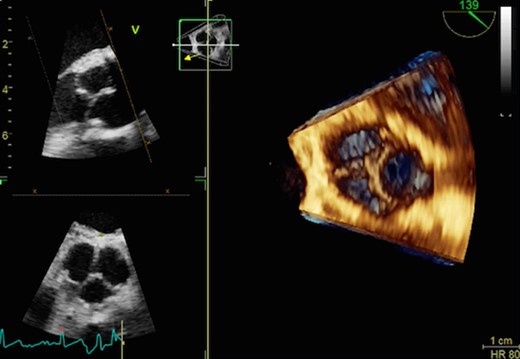

A 37-year-old male with diagnosis of OI was referred with exertional dyspnea. Echocardiographic examination showed severe degenerative aortic valve insufficiency, enlarged left ventricle (end diastolic diameter=64 mm) and decreased left ventricular ejection fraction (55%). Medical history revealed recurrent epistaxis and spontaneous bone fractures. An aortic valve intervention was planned based on the symptoms and echocardiographic results. Ozaki procedure was preferred choice of treatment related to bleeding tendency and the risk for prosthetic valve dehiscence. The technical details were described previously by Ozaki et al. [2]. Briefly, this technique can be described as the placement of the patient’s own pericardium into the aortic annulus following trimming and preparation according to the leaflet size (Fig. 1). Following the termination of cardiopulmonary bypass, transesophageal echocardiography showed no aortic valve regurgitation and gradient (2 mmHg) across the valve (Fig. 2). Postoperative follow-up was uneventful and the patient was discharged from the hospital on the fifth postoperative day. As an antiaggregant therapy just acetylsalicylic acid (300 mg) was prescribed. The transthoracic echocardiography showed no regurgitation or other pathological signs at one year follow-up.

Postoperative 3D echocardiographic view shows perfect competent neovalves.